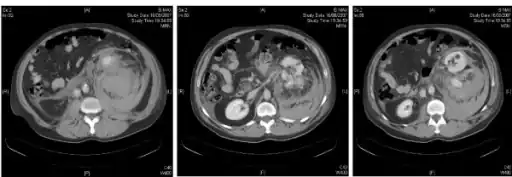

Retroperitoneal bleeding is an accumulation of blood in the retroperitoneal space. Signs and symptoms may include abdominal or upper leg pain, hematuria, and shock. It can be caused by major trauma or by non-traumatic mechanisms.

Diagnosis

Radiology

A magnetic resonance imaging (MRI) scan may be used to identify the collection of blood, although this is often not performed if bleeding is a medical emergency.[3]